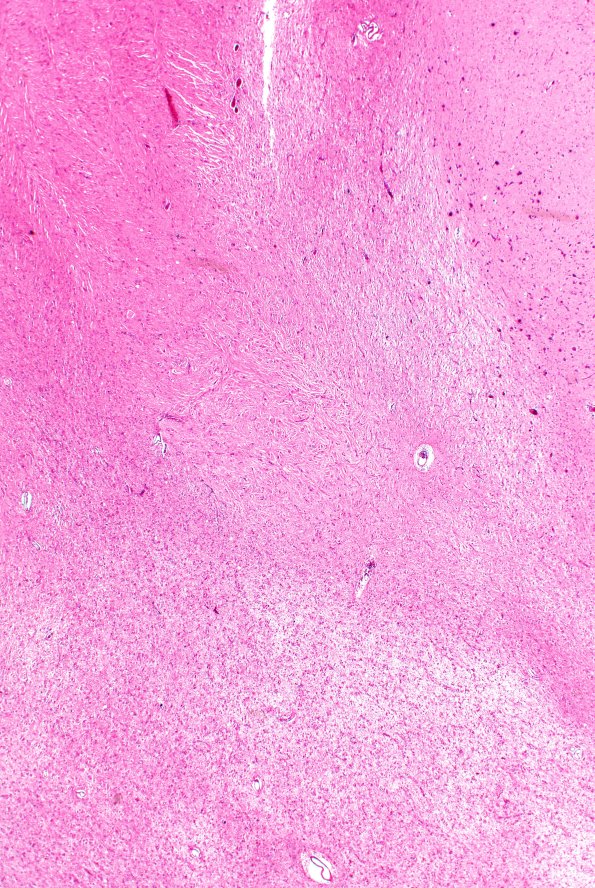

Washington University Experience | DEVELOPMENTAL MALFORMATIONS | Tuberous Sclerosis | 16B8 Tuber (Case 16) H&E 2XA

There are often unusual idiosyncratic features of tubers such as calcifications or, in this case, dense eosinophilic processes. (H&E)